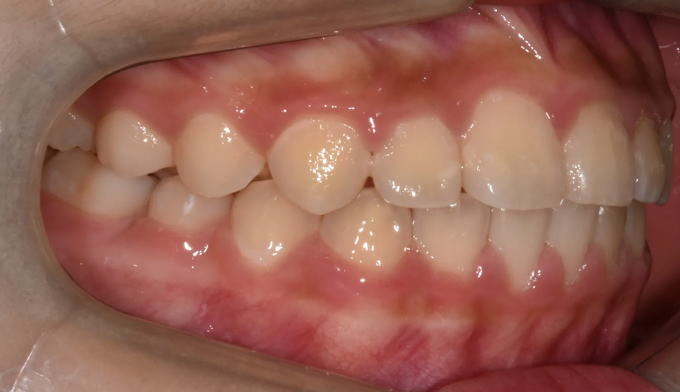

안모상으로는 반대교합도, 주걱턱도 심해보이지 않습니다.

하지만 엑스레이 검사시 주걱턱 경향이 심한 경우로 성장조절을 시작하였습니다.

1차교정 후 영구치가 다 나올때까지 지켜본 결과 1차교정으로 인해 보다 더 자연스러운 안모를 가지게 되었다고 생각합니다. 위턱이 아래턱 안에 갇혀있게 된다면 중안면부위의 결핍이 주걱턱 경향을 더 심하게 만들 가능성이 높기 때문입니다.